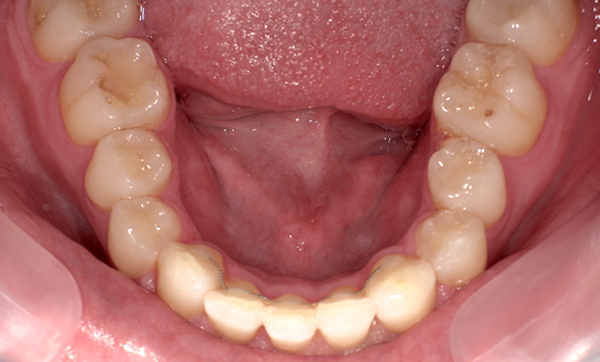

症例_009 「上下の前歯」症例

治療期間:7ヶ月金額:54万円+税20代女性捻転歯一部の反対咬合前歯のガタガタ